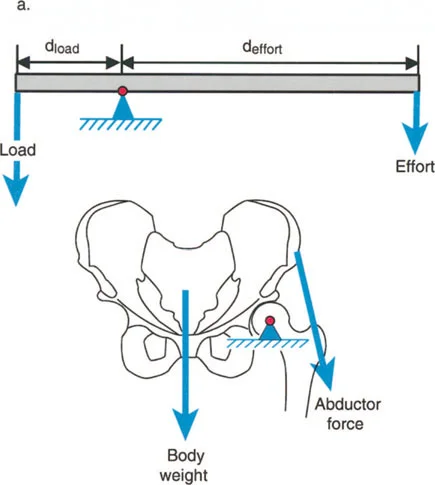

أمثلة أخرى رئيسية للتشوهات الديناميكية تشمل "الورم الفخذي المفرط" (Severe Femoral Anteversion) و "الورك الأفحج" (Coxa Vara). في كلتا هاتين الشذوذات المعمارية، يتم تقصير الطول الفيزيائي لذراع الرافعة لعضلات المبعدة (Abductor muscles) بشكل مرضي بسبب التشوه العظمي نفسه. قد تكون عضلة الألوية الوسطى (Gluteus Medius) صحية تمامًا، ومعصبة جيدًا، وقادرة على توليد قوة بيولوجية طبيعية، لكنها تعاني من خلل وظيفي سريري عميق لأن ميزتها الميكانيكية قد سُلبت بسبب الهندسة الهيكلية المتغيرة. هذه الفئة الفرعية المحددة من الأمراض تُعرف باسم "تشوه في طول ذراع الرافعة".

يشير خلل وظيفة الذراع الرافعة إلى التغيير المرضي في علاقات الرافعة الطبيعية بين ثلاثة مكونات حاسمة:

1. الحمل (The Load): الوزن أو المقاومة التي يجب التغلب عليها.

2. الجهد (The Effort): القوة العضلية المطبقة لتحريك الحمل.

3. موضع نقطة الارتكاز (The Fulcrum Position): المفصل الذي يحدث حوله الدوران.

بشكل خاص، يصف خلل وظيفة الذراع الرافعة حالة سريرية تتشوه فيها أذرع الرافعة الداخلية و/أو الخارجية بسبب سوء محاذاة العظام، أو التشوهات الالتوائية، أو تيبسات المفاصل الموضعية.

تاريخياً، كان جراحو العظام بطيئين في إدراك الأهمية القصوى لخلل وظيفة الذراع الرافعة، وغالبًا ما كانوا يركزون فقط على تحرير الأنسجة الرخوة أو نقل الأوتار. غالبًا ما يؤكد التدريب الجراحي على التفكير في العضلات على أنها مجرد مولدات طاقة بيولوجية. ومع ذلك، فإنه قانون أساسي في الفيزياء أن الطاقة لا يمكن توليدها أو نقلها أو استخدامها دون الاستفادة من أذرع الرافعة الهيكلية التي تتصل بها تلك العضلات.

بمجرد أن يبدأ الجراح في التفكير من حيث "العزوم" التي تولد القوة، بدلاً من مجرد انقباض عضلي معزول، فإنه يبدأ تلقائيًا في فحص النصف الآخر من المعادلة الميكانيكية: الرافعة نفسها.

بينما لا يستطيع الطب الحديث فعل الكثير لزيادة القوة البيولوجية الخام التي تولدها العضلة بشكل دائم (بخلاف العلاج الطبيعي)، يمكن غالبًا زيادة حجم العزم المؤثر على المفصل بشكل كبير ببساطة عن طريق تصحيح خلل وظيفة الذراع الرافعة جراحيًا. هذا هو جوهر النهج الذي يتبعه الأستاذ الدكتور محمد هطيف في علاج التشوهات العظمية المعقدة، حيث يركز على استعادة الميكانيكا الحيوية السليمة للجسم.

- الورك الأفحج (Coxa Vara): تشوه خلقي أو تطوري في عظم الفخذ يؤدي إلى تقصير ذراع الرافعة لعضلات الورك المبعدة، مما يضعف قدرتها على تثبيت الحوض.

- عرج ترندلنبورغ (Trendelenburg Lurch): في حالات ضعف عضلات الورك المبعدة (مثل الورك الأفحج)، يميل الحوض إلى السقوط على الجانب المقابل أثناء الوقوف على ساق واحدة، مما يؤدي إلى مشية متمايلة.